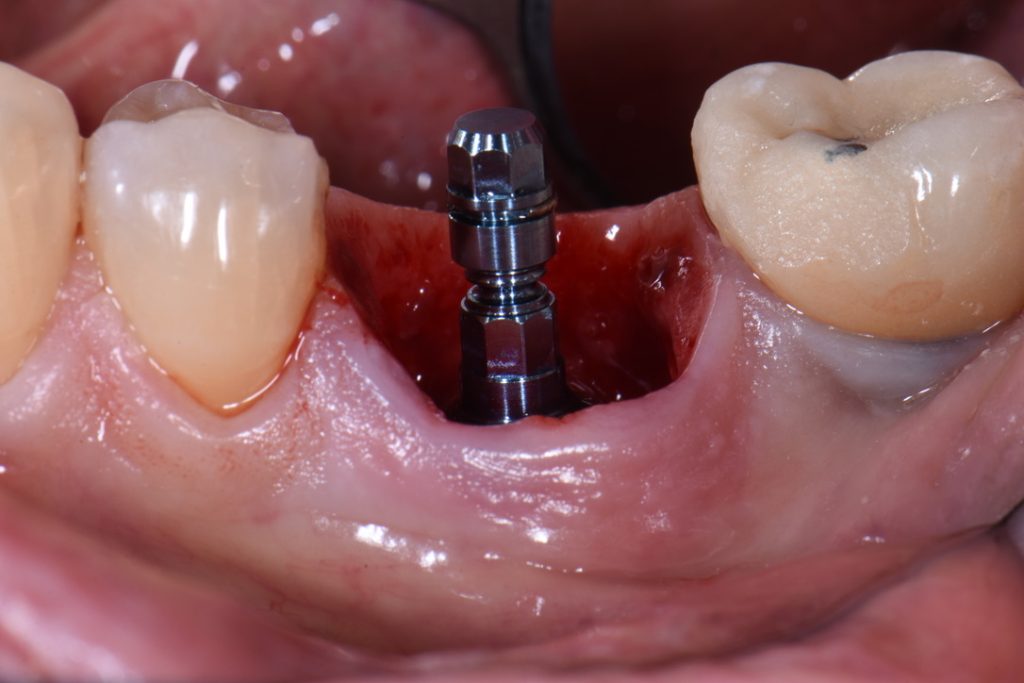

Once healing and bone integration are complete, your permanent replacement teeth are placed. In some cases, this can begin shortly after implant placement. Your treatment timeline will depend on healing progress and the complexity of your case.

We begin with impressions and bite records to fabricate your custom teeth and abutments. Some cases use standard components; others require custom options that may add time and cost. Each treatment is tailored precisely to your anatomy and needs.

Implant care is often a team effort. A dental surgeon will typically place the implants, while your general dentist manages your temporary and permanent restorations. Sometimes, other specialists may assist with parts of your treatment plan.